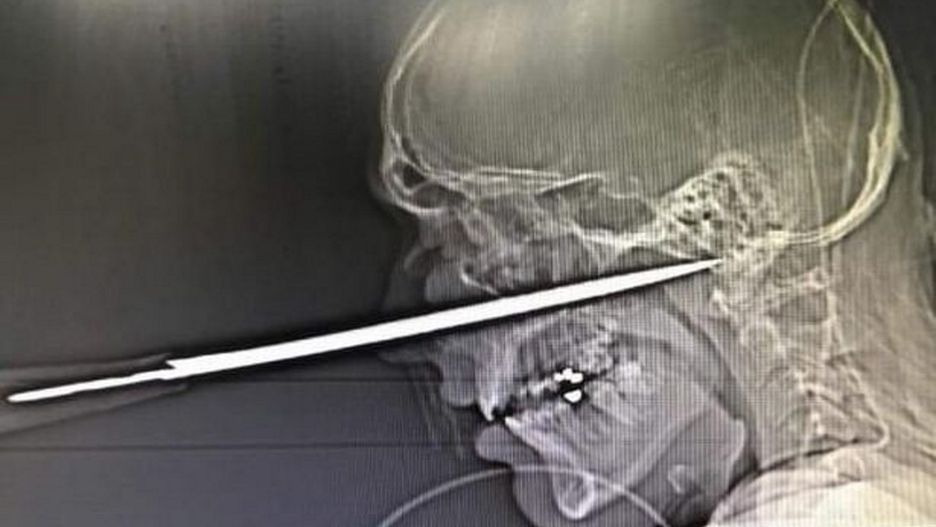

Robbie Pattinson, 21-letni angielski bokser amator, został ciężko ranny w trakcie bójki w pubie. Napastnik wbił mu w twarz nóż kuchenny. Gdyby ostrze wsunęło się o milimetr dalej, młody mężczyzna nie przeżyłby ataku.

Ostrze, które napastnik wbił 21-latkowi w twarz, mierzyło kilkanaście centymetrów. Lekarze stwierdzili, że bokserowi udało się uniknąć śmierci, ponieważ nóż ominął główną tętnicę. Od wykrwawienia i pewnej śmierci Pattinsona dzielił zaledwie milimetr.

Pattinson został wprowadzony w stan śpiączki klinicznej. Obudził się dwa dni po ataku. Po kolejnych trzech dniach 21-latek zaczął wracać do ćwiczeń na siłowni dla bokserów w Wigton. Według ustaleń "Mirror" młody mężczyzna chciał udowodnić, że nie zamierza porzucić sportu.

Robbie Pattinson czuje się całkiem dobrze i prawie wrócił do pełnej sprawności. Mężczyzna miewa zawroty i bóle głowy, nie czuje także lewej strony ust. Zaledwie 9 miesięcy po ataku 21-letni bokser zaczął przygotowywać się do najtrudniejszej walki w swojej karierze.